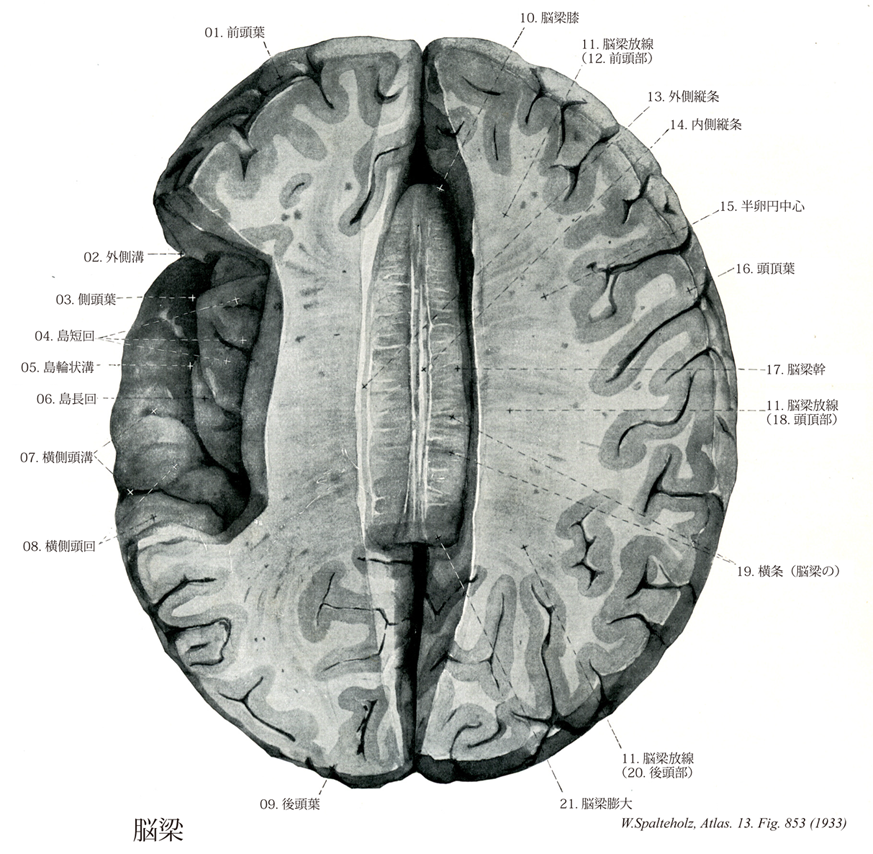

- 853_00【Corpus callosum脳梁 Corpus callosum】 Transverse nerve fibers connecting the two cerebral hemispheres at the base of the longitudinal cerebral fissure.

→(脳梁は左右の大脳皮質、ことに新皮質を結合する線維の集合したもので、系統発生的には最も新しく、ヒトでは非常に発育がよい。その前後経はほぼ7.7cmである。脳梁は正中断では全体としては釣針状で、4つの部分が区別される。後端部は膨大し、脳梁膨大といい、その前方に続いて水平に走る部分を脳梁幹とよぶ脳梁はその前端では強く屈曲し、脳梁膝をつくる。これはさらに後下方にくちばしのように尖って脳梁吻となり、しだいに薄くなって終板に続く。)

- 853_10【Genu of corpus callosum脳梁膝 Genu corporis callosi】 Knee of the corpus callosum situated anterosuperior to the rostrum.

→(脳梁膝は脳梁の前端部で下方と後方にひだを形成し脳梁吻で終わる。線維は前方に向かって走り、前頭葉に放散している(小鉗子)。)

- 853_11【Radiation of corpus callosum脳梁放線 Radiatio corporis callosi】 Fibers radiating from the corpus callosum to the cerebral cortex.

→(脳梁放線は左右の大脳半球の半卵円中心に放射する脳梁の線維群。脳梁の線維群は大脳縦裂の床に当たる部位を横断し、側脳室の天井の大部分を形成しており、種々の皮質領域に分布する時、豊富な脳梁放線として扇状に広がる。)

- 853_13【Lateral longitudinal stria外側縦条 Stria longitudinalis lateralis】 Paired, longitudinal band of nerve fibers on the corpus callosum that is covered laterally by the cingulate gyrus. It receives efferent fibers from the hippocampus.

→(外側縦条は帯状回の両外側縁の近くで、灰白質を伴って前後に走る細い縦条。嗅脳の一部。)

- 853_14Lancisi, Stria of【Medial longitudinal stria内側縦条 Stria longitudinalis medialis】 Medial band of longitudinal nerve fibers on the corpus callosum. It receives efferent Fibers from the hippocampus.

→(内側縦条は脳梁幹の表面で正中線の両端を、灰白質を伴って前後に走る細長い縦条。外側縦条とともに脳梁幹背面の灰白質を一部すなわち灰白質層、海馬の痕跡を形成する。嗅脳の一部。)

- 853_15【Semioval center半卵円中心;卵半円中心 Centrum semiovale】

→(大脳皮質の白質のすべてに共通して中心部になる部分には、交連、連合、投射線維が含まれているが、大脳を水平段にすると、卵円形に見えるので、半卵円中心と呼ぶ。 脳梁の上方で帯状回を通る水平断面で最大に現れ、やや卵半円形をなすので、これを半卵円中心と称する。)

- 853_17【Trunk of corpus callosum; Body of corpus callosum脳梁幹;脳梁体 Truncus corporis callosi】 Portion between the splenium and genu of corpus callosum.

→(脳梁幹は脳梁膨大と脳梁膝の間の主に脳梁の弓状部分。)

- 853_19【Transversal striae横条(脳梁の) Striae transversae】

- 853_21【Splenium of corpus callosum脳梁膨大 Splenium corporis callosi】 Bulging, exposed posterior end of corpus callosum.

→(脳梁膨大は脳梁幹の後端は著しく膨大化し、松果体と蓋板とを上方から被っている。膨大部と中脳との間の大脳横裂からは脳軟膜が進入し、脈絡組織を形成する。)